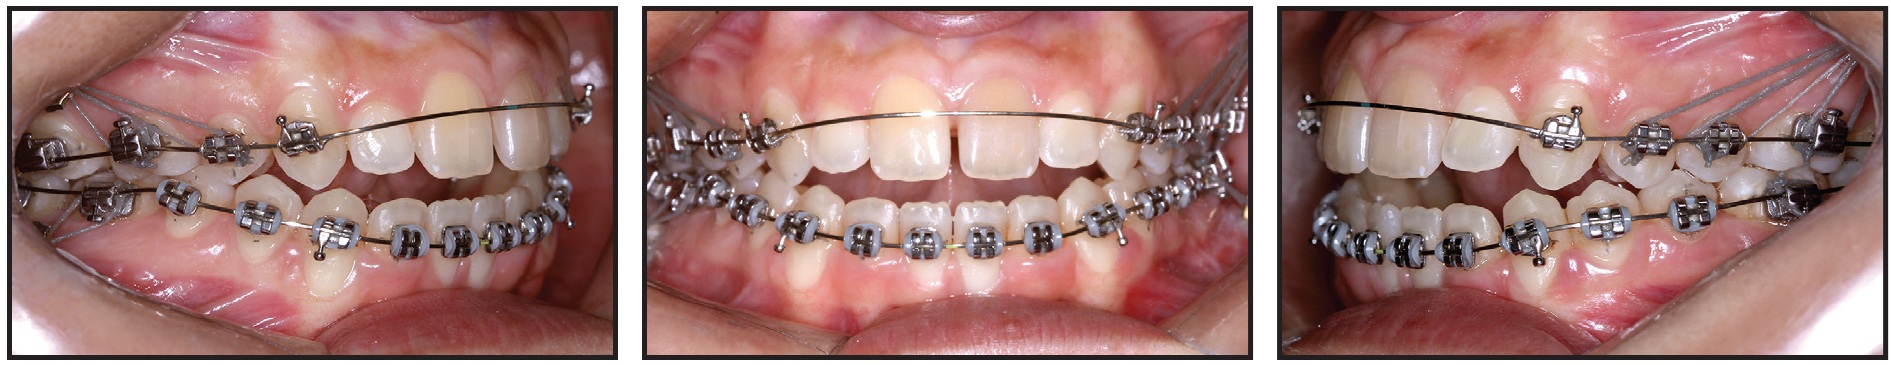

On the same day as the miniplate installation, orthodontic treatment began with placement of .018" × .028" Ricketts-prescription fixed appliances and .012" nickel titanium archwires in both arches (Fig. 5). The first molars were anchored to the miniplates with elastomeric ligatures. The upper central and lateral incisors were not included in the archwires while endodontic treatment of the central incisors was still in progress.

After 21 days of leveling and alignment, .016" × .016" Titanol* thermoactivated archwires (80g) were placed, followed by .016" × .022" thermoactivated wires (120g) in both arches (Fig. 6).

Fig. 5 Fixed appliances bonded on day of surgery; .012" nickel titanium archwires inserted and first molars anchored to miniplates with elastomeric ligatures.

Fig. 6 After 21 days of leveling and alignment.

The premolars were included in these mechanics, supported by the miniplate anchorage. Because of the more superior positioning of the upper miniplates and the more inferior positioning of the lower miniplates, with both placed posteriorly on the vestibular side, bone remodeling was achieved in three planes of space, producing simultaneous intrusion, distalization, and labial tipping forces.

Correction of the anterior open bite, with a slightly positive vertical overjet, was observed after three months of treatment (Fig. 7).

Fig. 7 After three months of treatment, showing correction of anterior open bite and buccal inclination of upper first molars as side effect of intrusive mechanics.

An increased buccal tipping of the upper first molars was noted, with the palatal cusps contacting the buccal cusps of the lower left first molar and lower right second premolar and first molar—a side effect of the force produced by the miniplate attachment to the upper molar tubes. To control the molar tipping, an .016" × .022" Titanol Low-Force* archwire with a lower archform was inserted in the upper arch. The thicker wire, tied tightly with metallic ligatures, promoted slight compression of the upper arch and better torque control of the upper posterior teeth.

During this phase, the patient was referred for speech therapy evaluation. Nogueira** spurs were added to the lingual surfaces of the upper and lower incisors to help eliminate the tongue interpositioning habit.

After five months of treatment, when the endodontic therapy was complete, the upper incisors were bonded and incorporated into the archwire (Fig. 8). The upper posterior teeth were kept anchored to the miniplates using metallic wires coated with flowable resin for patient comfort.

Fig. 8 After five months of treatment, upper incisors bonded and incorporated into archwire; metallic wires coated with flowable resin used to anchor upper posterior teeth to miniplates.